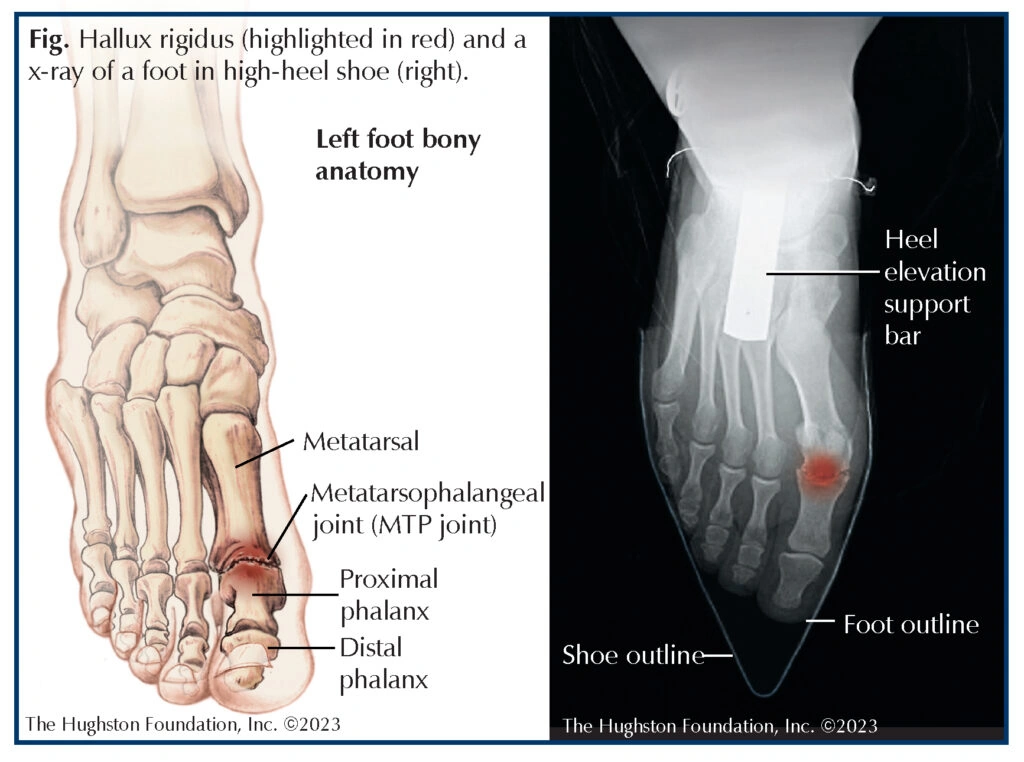

First up, what on earth is hallux rigidus? It’s basically a fancy way to say, “my big toe joint is stiff and cranky.” The medical term for the big toe joint is the metatarsophalangeal joint[6], and when arthritis sets up shop there, it goes by the name hallux rigidus.

Let me pull the curtain back on foot anatomy for a second. That metatarsophalangeal joint is the point where the first long bone in your foot (your metatarsal) meets the base of your big toe (your proximal phalanx)[3][6]. You use it for everything—walking, running, even just standing in line at the grocery store.

When the smooth cartilage at this joint starts to wear down (think of it as losing the Teflon coating on your favorite pan), bones start rubbing together. Ouch. The result? Stiffness, pain, and sometimes those little bone bumps called osteophytes. This messes with your ability to push off—making you feel awkward and unsteady.